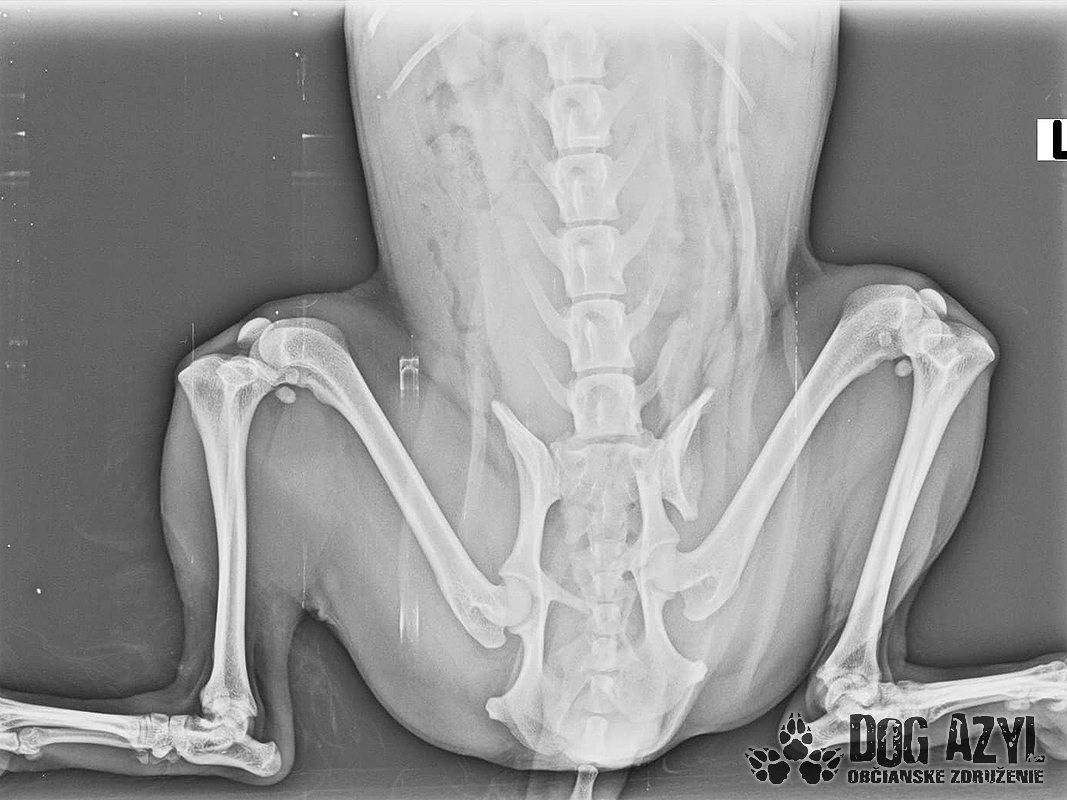

Mia, narodená máj 2015, sa našla zrazená v obci Bodza. Mala obrovské šťastie, že ju nálezkyňa ihneď naložila do auta a utekala s ňou k nášmu veterinárovi. Bola v katastrofálnom stave a mala obrovské bolesti :( Keďže Mia bola čipovaná, hneď sme sa dopátrali aj k majiteľom, ale na druhej strane telefónu nám bolo oznámené, že Miu darovali niekomu ale nemajú kontakt. Tak sme trocha pátrali a vypátrali sme, že Mia bola darovaná "do dobrých rúk" z postele priamo na dvor! Rodina sa tvárila veľmi zodpovedne a láskyplno, ale zrejme nepochopili,že Mia je kastrovaná a už nebude produkovať šteniatka. Po pár neúspešných pokus spáriť ju so samcom putovala do ďalších dobrých rúk" a to k miestnemu alkoholikovi, kde skončila v šope na reťazi a spala na kope hnoja :( Podarilo sa jej nejakým zázrakom ujsť, ale žiaľ skončila pod kolesami auta. Čomu sa vlastne ani nečudujeme, keďže cez tie zlepené chlpy nemala najmenšiu šancu vidieť pred seba. Mia podstúpila veľmi náročnú operáciu panvy, ktorá sa úspešne podarila, ale pri chladnejšom počasí zvykne trocha krívať. Mala tiež zlomený pst na zadnej nohe, ktorý sa zle zrástol a tak jej nechtík rastie trocha krivo a treba ho pravidelne strihať. Vôbec nič jej to však neuberá na kráse a chuti do života :) Mia si hľadá rodinu, ktorá jej vie sľúbiť, že ju nikdy viac neopustí. Je to skôr pokojná fenka, nie je vôbec náročná na pohyb ale na maznanie o to viac :) Veľmi rada sa túli k človeku, je veľmi priateľská a kontaktná. Vôbec jej nevadí spoločnosť iných psíkov ani mačiek ale nepotrebuje ich ku svojej spokojnosti :) Mia je dokonale vhodná do bytu, ale k malým deťom určite nie, má totiž rada svoje súkromie. Ak by sa mala adoptovať k rodinnému domu tak podmienkou je bývanie v dome.